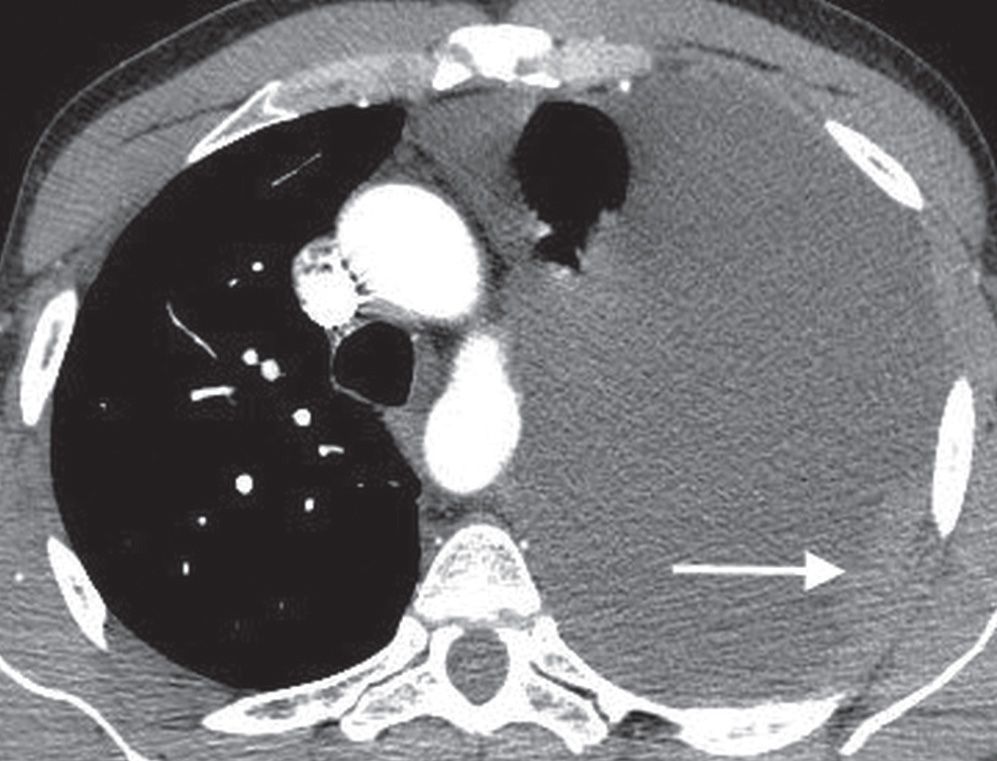

Fluid Around Lung Ct Scan

Fluid Around Lung Ct Scan Lungs Filled With Fluid Cancer For those suffering from lung cancer, the respiratory. Symptoms of pleural effusion can be different. Called pleural effusion, fluid is fairly common in people with lung cancer and can be caused by the disease itself or some treatments. Pulmonary edema is an accumulation of extravascular fluid in the lungs affecting the respiratory system, making it difficult to breathe. Doctors can. Lungs Filled With Fluid Cancer.